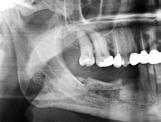

grænsning af canalis mandibulae. I præmolarregionen er det også relevant at identificere foramen mentale. Til det formål anvendes røntgenoptagelser, som desuden vil kunne afsløre patologiske tilstande, der skal behandles før implantatindsættelsen. Periapikale røntgenoptagelser har typisk en forholdsvis høj billedopløsning og vil i teorien være ideelle til at visualisere fx canalis mandibulae. Ulempen er den begrænsede størrelse af billedfeltet, hvorfor det kan være vanskeligt at få relevante anatomiske strukturer gengivet på billedet i hele deres udstrækning. Panoramabilleder dækker et større område af kæben og er, på trods af en lidt ringere billedopløsning i forhold til periapikale optagelser, derfor ofte oplagte ved implantatplanlægningen, specielt hvis det drejer sig om større behandlinger med indsættelse af flere implantater. Panoramabilledet giver et godt overblik over hele tandsættet og kæberne, hvormed patologiske tilstande, som skal behandles inden eventuel implantatbehandling, kan identificeres. I visse tilfælde kan det være relevant at anvende segmenterede optagelser, så man fx ved planlægning posteriort i mandiblen kan fravælge bestråling af øvrige områder og hermed reducerer stråledosis.

Da et implantat ideelt set skal være omgivet af 1-2 mm knogle langs hele implantatoverfladen, vil der i tilfælde af en smal knoglekam være risiko for, at implantatet bliver placeret dybt, hvor implantatets skulder således forsænkes i forhold til den mest marginale begrænsning af processus alveolaris. Dette kan bl.a. medføre en uhensigtsmæssig krone-implantat-ratio. Klinisk og radiologisk vurdering af knoglens bredde er derfor også nødvendig for at kunne bestemme den mest optimale implantatlængde, inklusive om der er behov for horisontal knogleopbygning enten før eller i forbindelse med implantatindsættelsen (Fig. 3). Dette er naturligvis ikke muligt med todimensionale (2-d) røntgenoptagelser, og en klinisk vurdering af breddeforholdene med palpation og evt. ”ridge mapping” (9) eller ved hjælp af tredimensionale (3-d) røntgenoptagelser vil derfor ofte være nødvendig. Det skal her nævnes, at en 3-d-optagelse også kan afklare, hvordan canalis mandibulae er orienteret i det facioorale plan, hvilket ligeledes kan influere på behandlingsplanlægningen.

Undersøgelser har vist, at canalis mandibulae er mere synlig på CBCT-snitbilleder end på panoramabilleder (13,14). En undersøgelse fandt, at canalis mandibulae og foramen mentale kunne identificeres på alle de undersøgte CBCT-billeder af yngre personer og med god visibilitet af canalis mandibulae på 51 % og foramen mentale på 98,5 % af billederne (13). På panoramabillederne kunne canalis mandibulae udelukkende identificeres på 93 % af billederne (12 % med god visibilitet) og foramen mentale på 45 % af billederne (0 % med god visibilitet). En anden undersøgelse viste endvidere, at canalis mandibulae på både CBCT- og panoramabilleder er mest synlig svarende til den distale del af kanalen, og at synligheden afhænger af kanalens forløb, hvor det var sværest at se kanaler med et lineært (lige linje, modsat et elliptisk, skeformet eller knækket) kurveforløb (14). Af og til kan det være svært at identificere canalis mandibulae i et specifikt område, hvor implantatindsættelsen er planlagt, og man kan også forveksle kanalen med et marvrum i knoglen på rekonstruerede CBCT-

Udover en god visualisering af de nævnte strukturer er det naturligvis også afgørende, at måling af dimensioner og afstande er pålidelig på røntgenbillederne. Det er velkendt, at der for 2-d-optagelser ses projektionsforstørrelse (15,16). Det er vist, at en forstørrelse horisontalt og vertikalt på 5-10 % gennemsnitligt skal påregnes på periapikale optagelser med parallelteknik (17). Forstørrelsen varierer dog meget og afhænger primært af afstanden mellem objektet og receptoren. For panoramaapparatur anfører fabrikanterne typisk en forstørrelsesgrad på 20-25 % i gennemsnit, men ovennævnte undersøgelse viste, at forstørrelsen på panoramaoptagelser varierer meget fra optagelse til optagelse med forskelligheder i de to plan og i forskellige regioner (17). I den forbindelse skal det nævnes, at positioneringen af patienten i røntgenapparatet har stor betydning for projektionsforstørrelsen. Patienten skal placeres korrekt i apparatet i forhold til midterplanet (lodret), Frankfurt-horisontalplanet samt hjørnetandslyslinjen, således at kæberne ligger inden for skarphedszonen. Det er således afgørende, at der kompenseres for forstørrelsen ved målinger på billederne. En metode til dette er kuglekalibrering, hvor man ved placering af en metalkugle med kendte dimensioner (typisk Ø 5 mm) i det aktuelle område efterfølgende kan beregne den reelle forstørrelse (17). Da forstørrelsen, som sagt, varierer afhængigt af region (maksil/mandibel, anteriort/posteriort), skal kuglen placeres så tæt som muligt på det sted, hvor implantatet planlægges indsat (Fig. 5). Det betyder, at der skal anvendes en kugle for hvert implantatsted. Korrekt placering